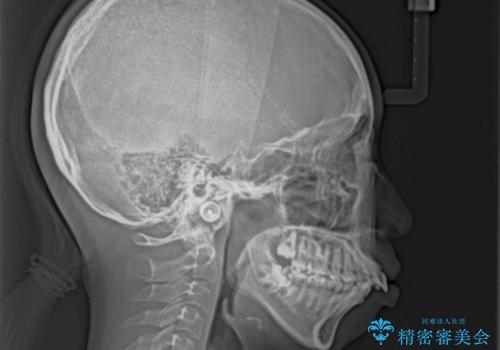

- 上顎前歯が飛び出していて唇がうまく閉じられないとのことで来院された患者様です。

くちばしのように前歯が突出していたため、口元を積極的に引っ込めるために、上下左右の小臼歯4本を抜歯することとしました。

また、上顎歯列が下顎に対して前方位に位置していたため、補助装置を用いて上顎歯列を後方に移動させ、より積極的に口元を下げるようにしました。

上下正中位置を改善するため、左下はイレギュラーに第二小臼歯を抜歯しました。そのため治療期間の長期化が予想されましたが、2年半ほどで期待通りの歯列に仕上げることができました。